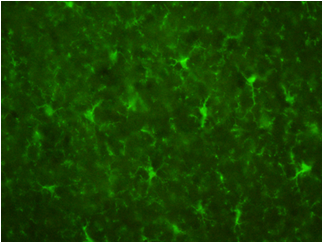

数据提供:创价大学理工学部中嶋老师

样本:大鼠(左)以及小鼠(右)大脑皮质冰冻切片

一抗:抗Iba1,山羊多克隆抗体(1:250)

二抗:Alexa Fluor488标记抗山羊IgG